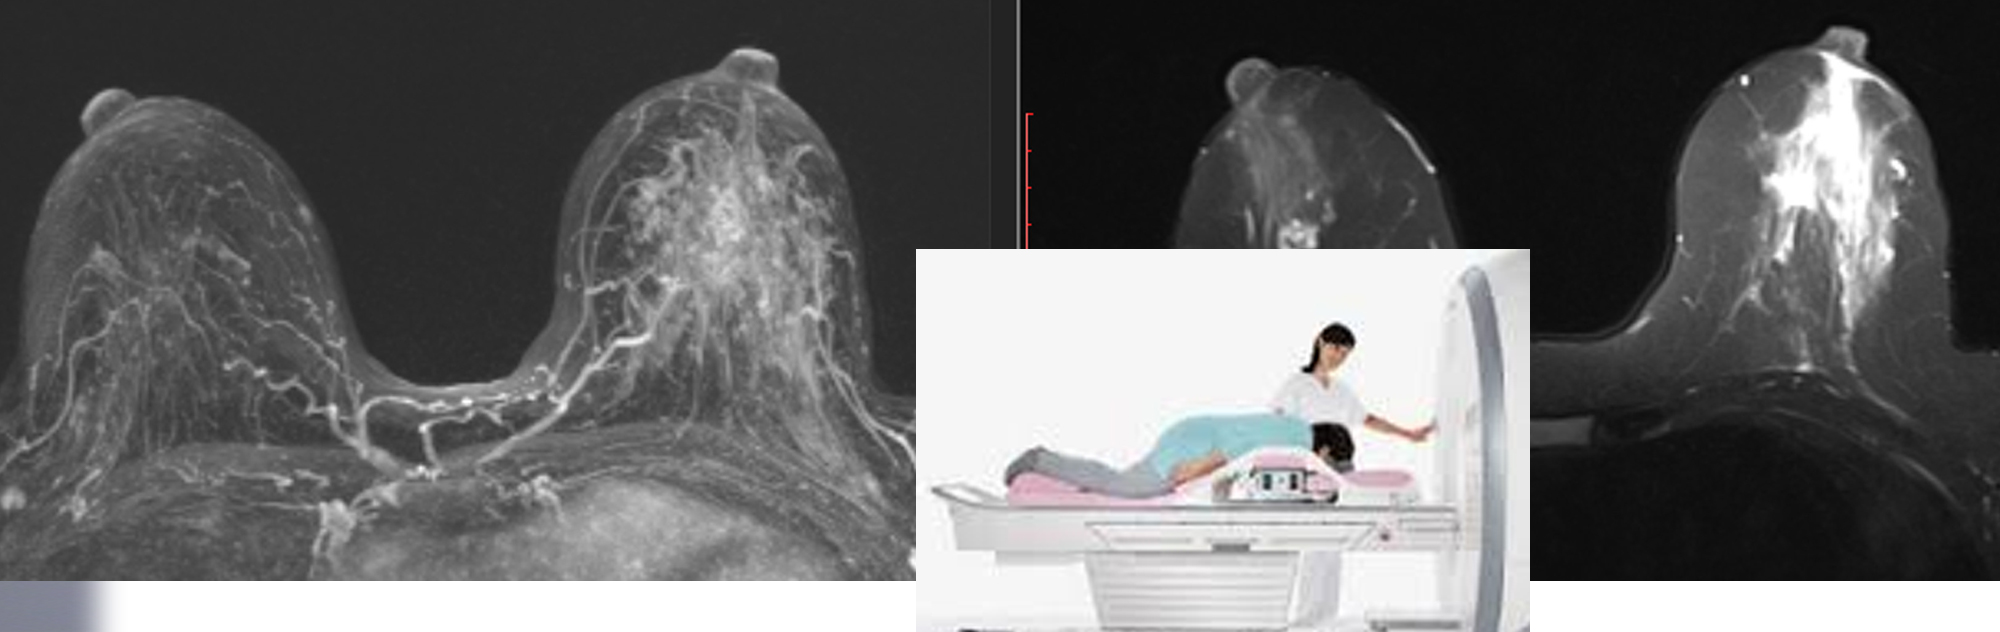

How is Breast MRI performed?

During a Breast MRI exam, a dye (contrast agent) may be injected through an intravenous (IV) line in your arm to enhance the tissues or blood vessels on the MRI pictures. You will lie face down on a comfortable, padded scanning table. Your breasts fit into cushioned openings in the table, which contains coils that detect magnetic signals from the MRI machine. The table then slowly slides into the opening of the MRI machine. The images are then recorded on a computer.